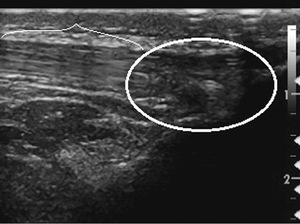

Pacjent, lat 52, zgłosił się do lekarza ortopedy z powodu silnego bólu w okolicy prawej pięty, który wystąpił nagle poprzedniego dnia podczas treningu piłki nożnej. Pacjent uprawia sport regularnie. Do tej pory nie cierpiał z powodu żadnych dolegliwości bólowych tej okolicy, a początek bólu nie był związany z bezpośrednim urazem. Podczas badania stopy okolica ścięgna Achillesa (piętowego) była obrzęknięta i bolesna, ruchy czynne w stawie skokowym znacznie ograniczone. Stwierdzono brak palpacyjnej bolesności w okolicy kostki przyśrodkowej i bocznej z zachowaną stabilnością w ruchach na boki.

Obrzęknięta okolica ścięgna Achillesa wraz z nagłym początkiem dolegliwości wskazuje na jego zerwanie. Niemniej możliwość wykonywania czynnych ruchów w stawie skokowym, nawet w niewielkim zakresie, przemawia za innym rozpoznaniem. Nie występuje też wyczuwalna luka w ścięgnie, jednak może być ona maskowana obrzękiem tej okolicy. Zapalenie kaletki głębokiej ścięgna Achillesa również może wywołać podobne objawy. Często wiąże się ono z występowaniem wyrośli kostnej na kości piętowej (deformacja Haglunda), która drażniąc kaletkę, wywołuje jej stan zapalny. Do złamań zmęczeniowych kości piętowej najczęściej dochodzi u żołnierzy oraz sportowców, którzy biegają długie dystanse po twardym podłożu. Jednakże w tym wypadku jest to mało prawdopodobne rozpoznanie, ponieważ pacjent może stanąć na pięcie oraz nie ma krwiaka i obrzęku tej okolicy.